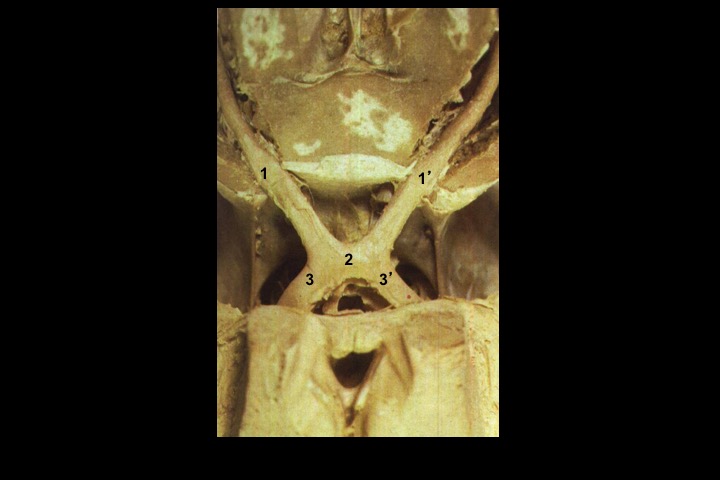

O Prof. Emérito da UFRJ Dr. Adalmir Morterá Dantas está disponibilizando através de nosso website e de nosso canal youtube (cursobom) o Museu de Neuroanatomia, no intuito de promover esta área de conhecimento junto aos estudantes de Medicina.

As figuras são apresentadas em 4 vídeos no youtube e podem ser obtidas via download clicando-se na figura em questão.